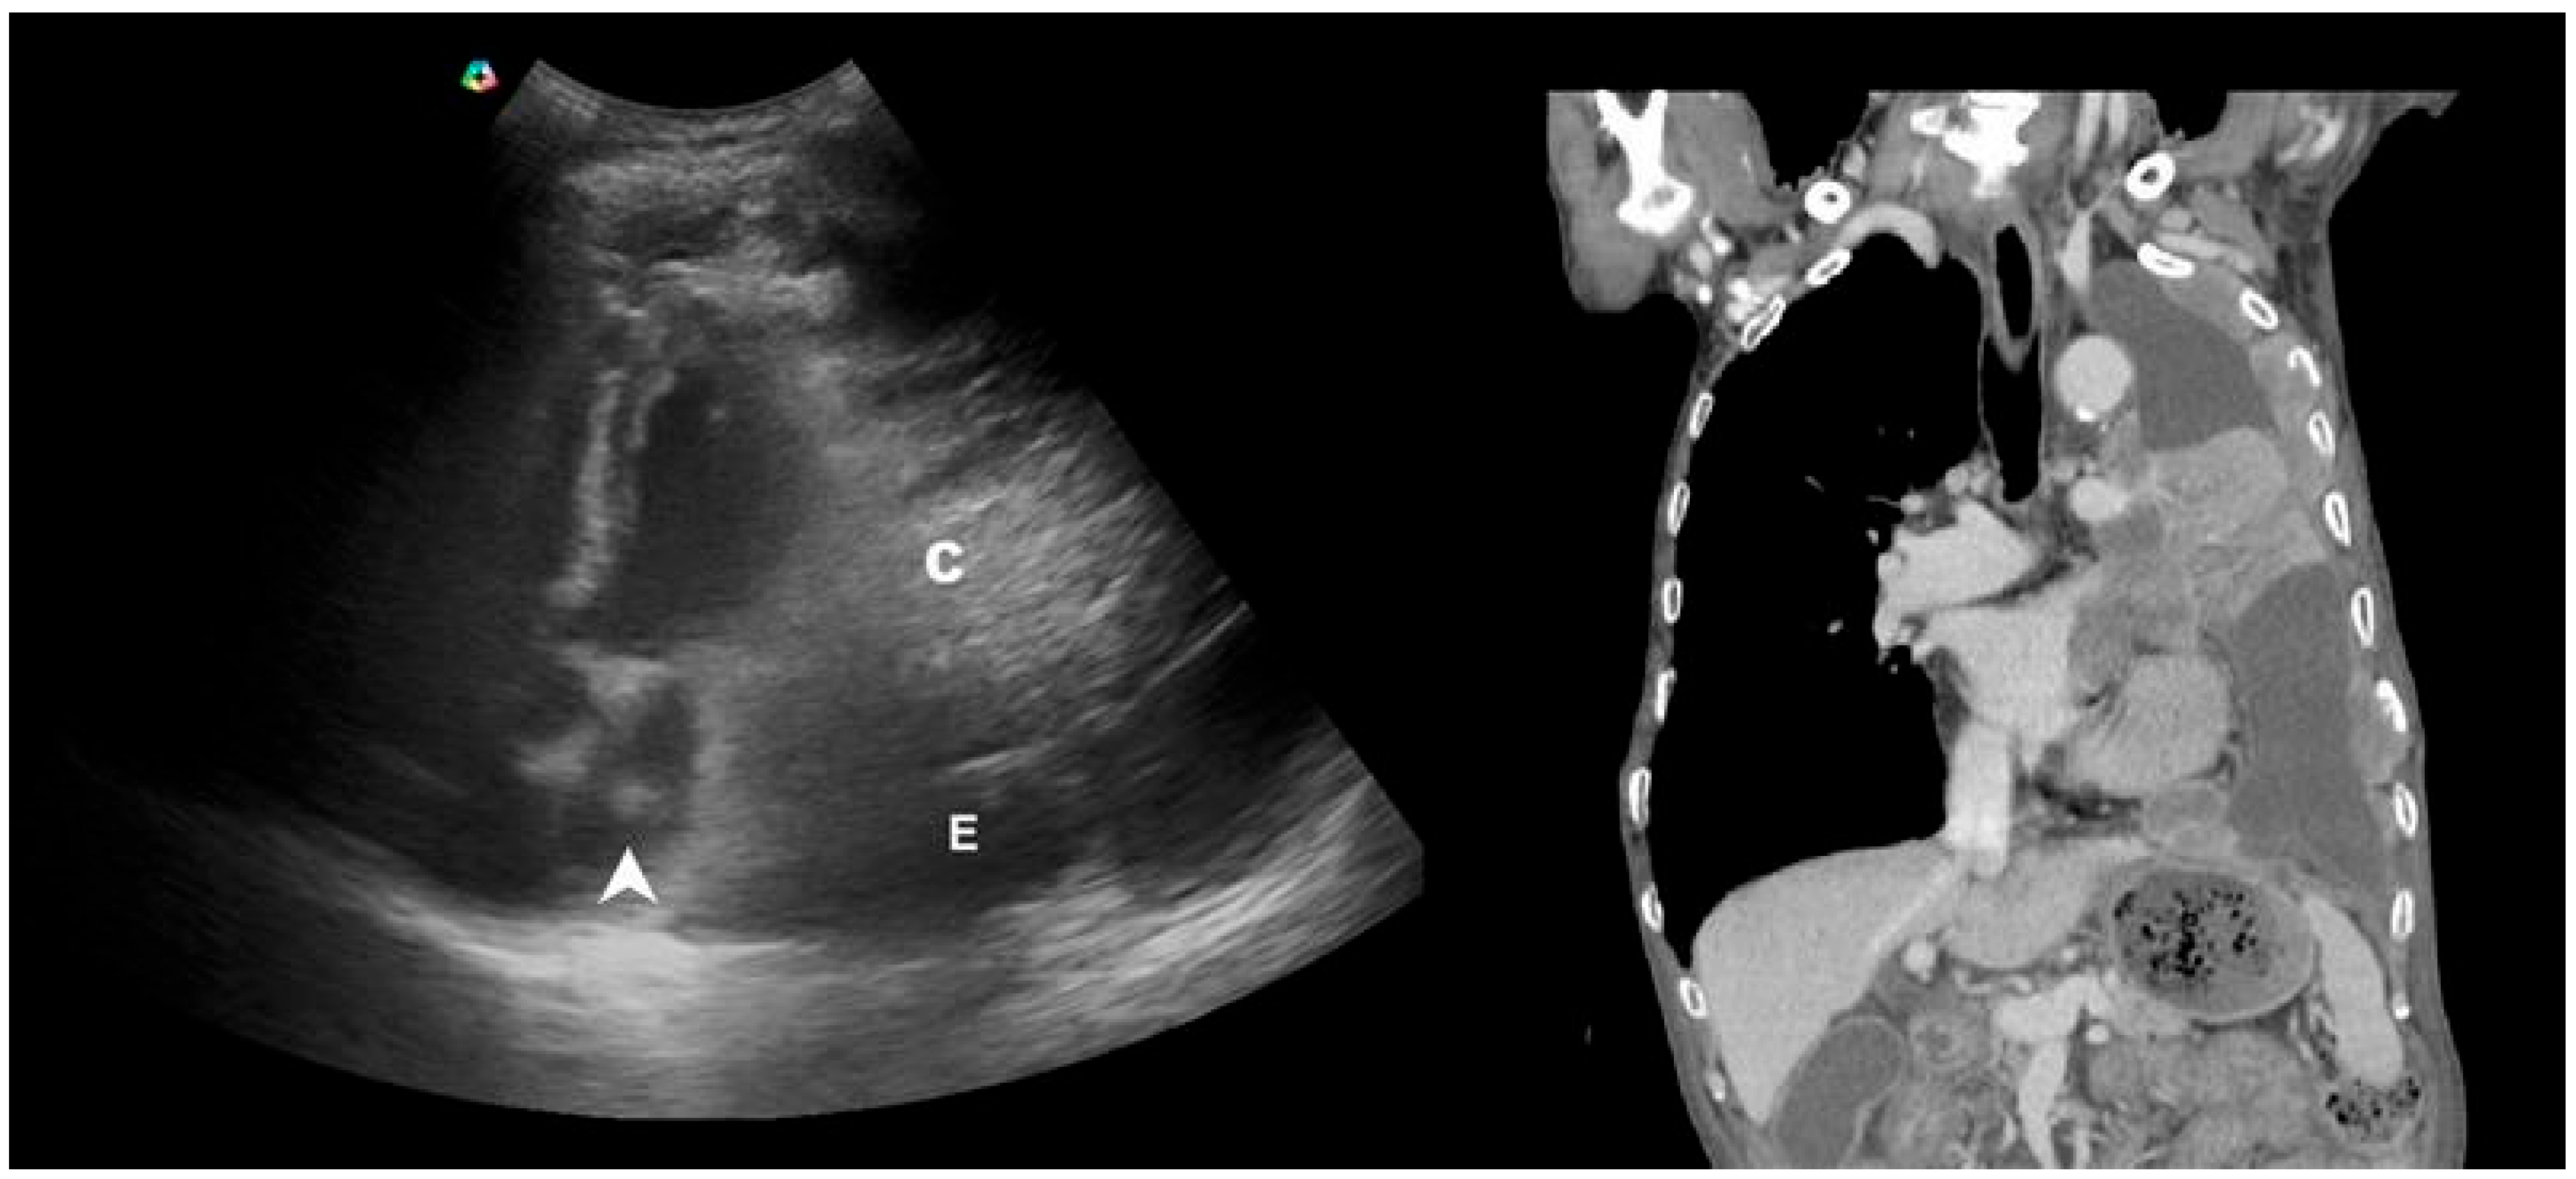

- Ko, Y.; Tobino, K.; Yasuda, Y.; Sueyasu, T.; Nishizawa, S.; Yoshimine, K.; Munechika, M.; Asaji, M.; Yamaji, Y.; Tsuruno, K.; et al. A Community-acquired Lung Abscess Attributable to Streptococcus pneumoniae which Extended Directly into the Chest Wall. Intern. Med. 2017, 56, 109–113. [Google Scholar] [CrossRef][Green Version]

- Hsu, N.C.; Tseng, C.L.; Yang, C.W.; Hsu, C.H. Man With Dyspnea. Ann Emerg Med. 2022, 79, e105–e106. [Google Scholar] [CrossRef]